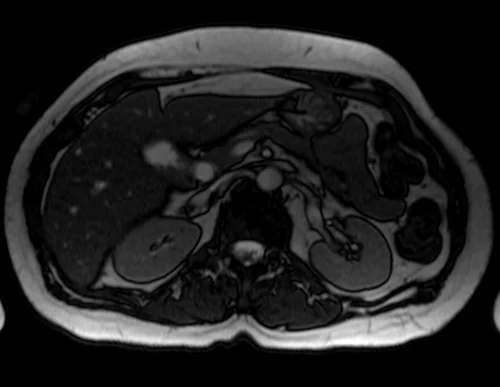

mrcp axial trufi image 4 - MRI